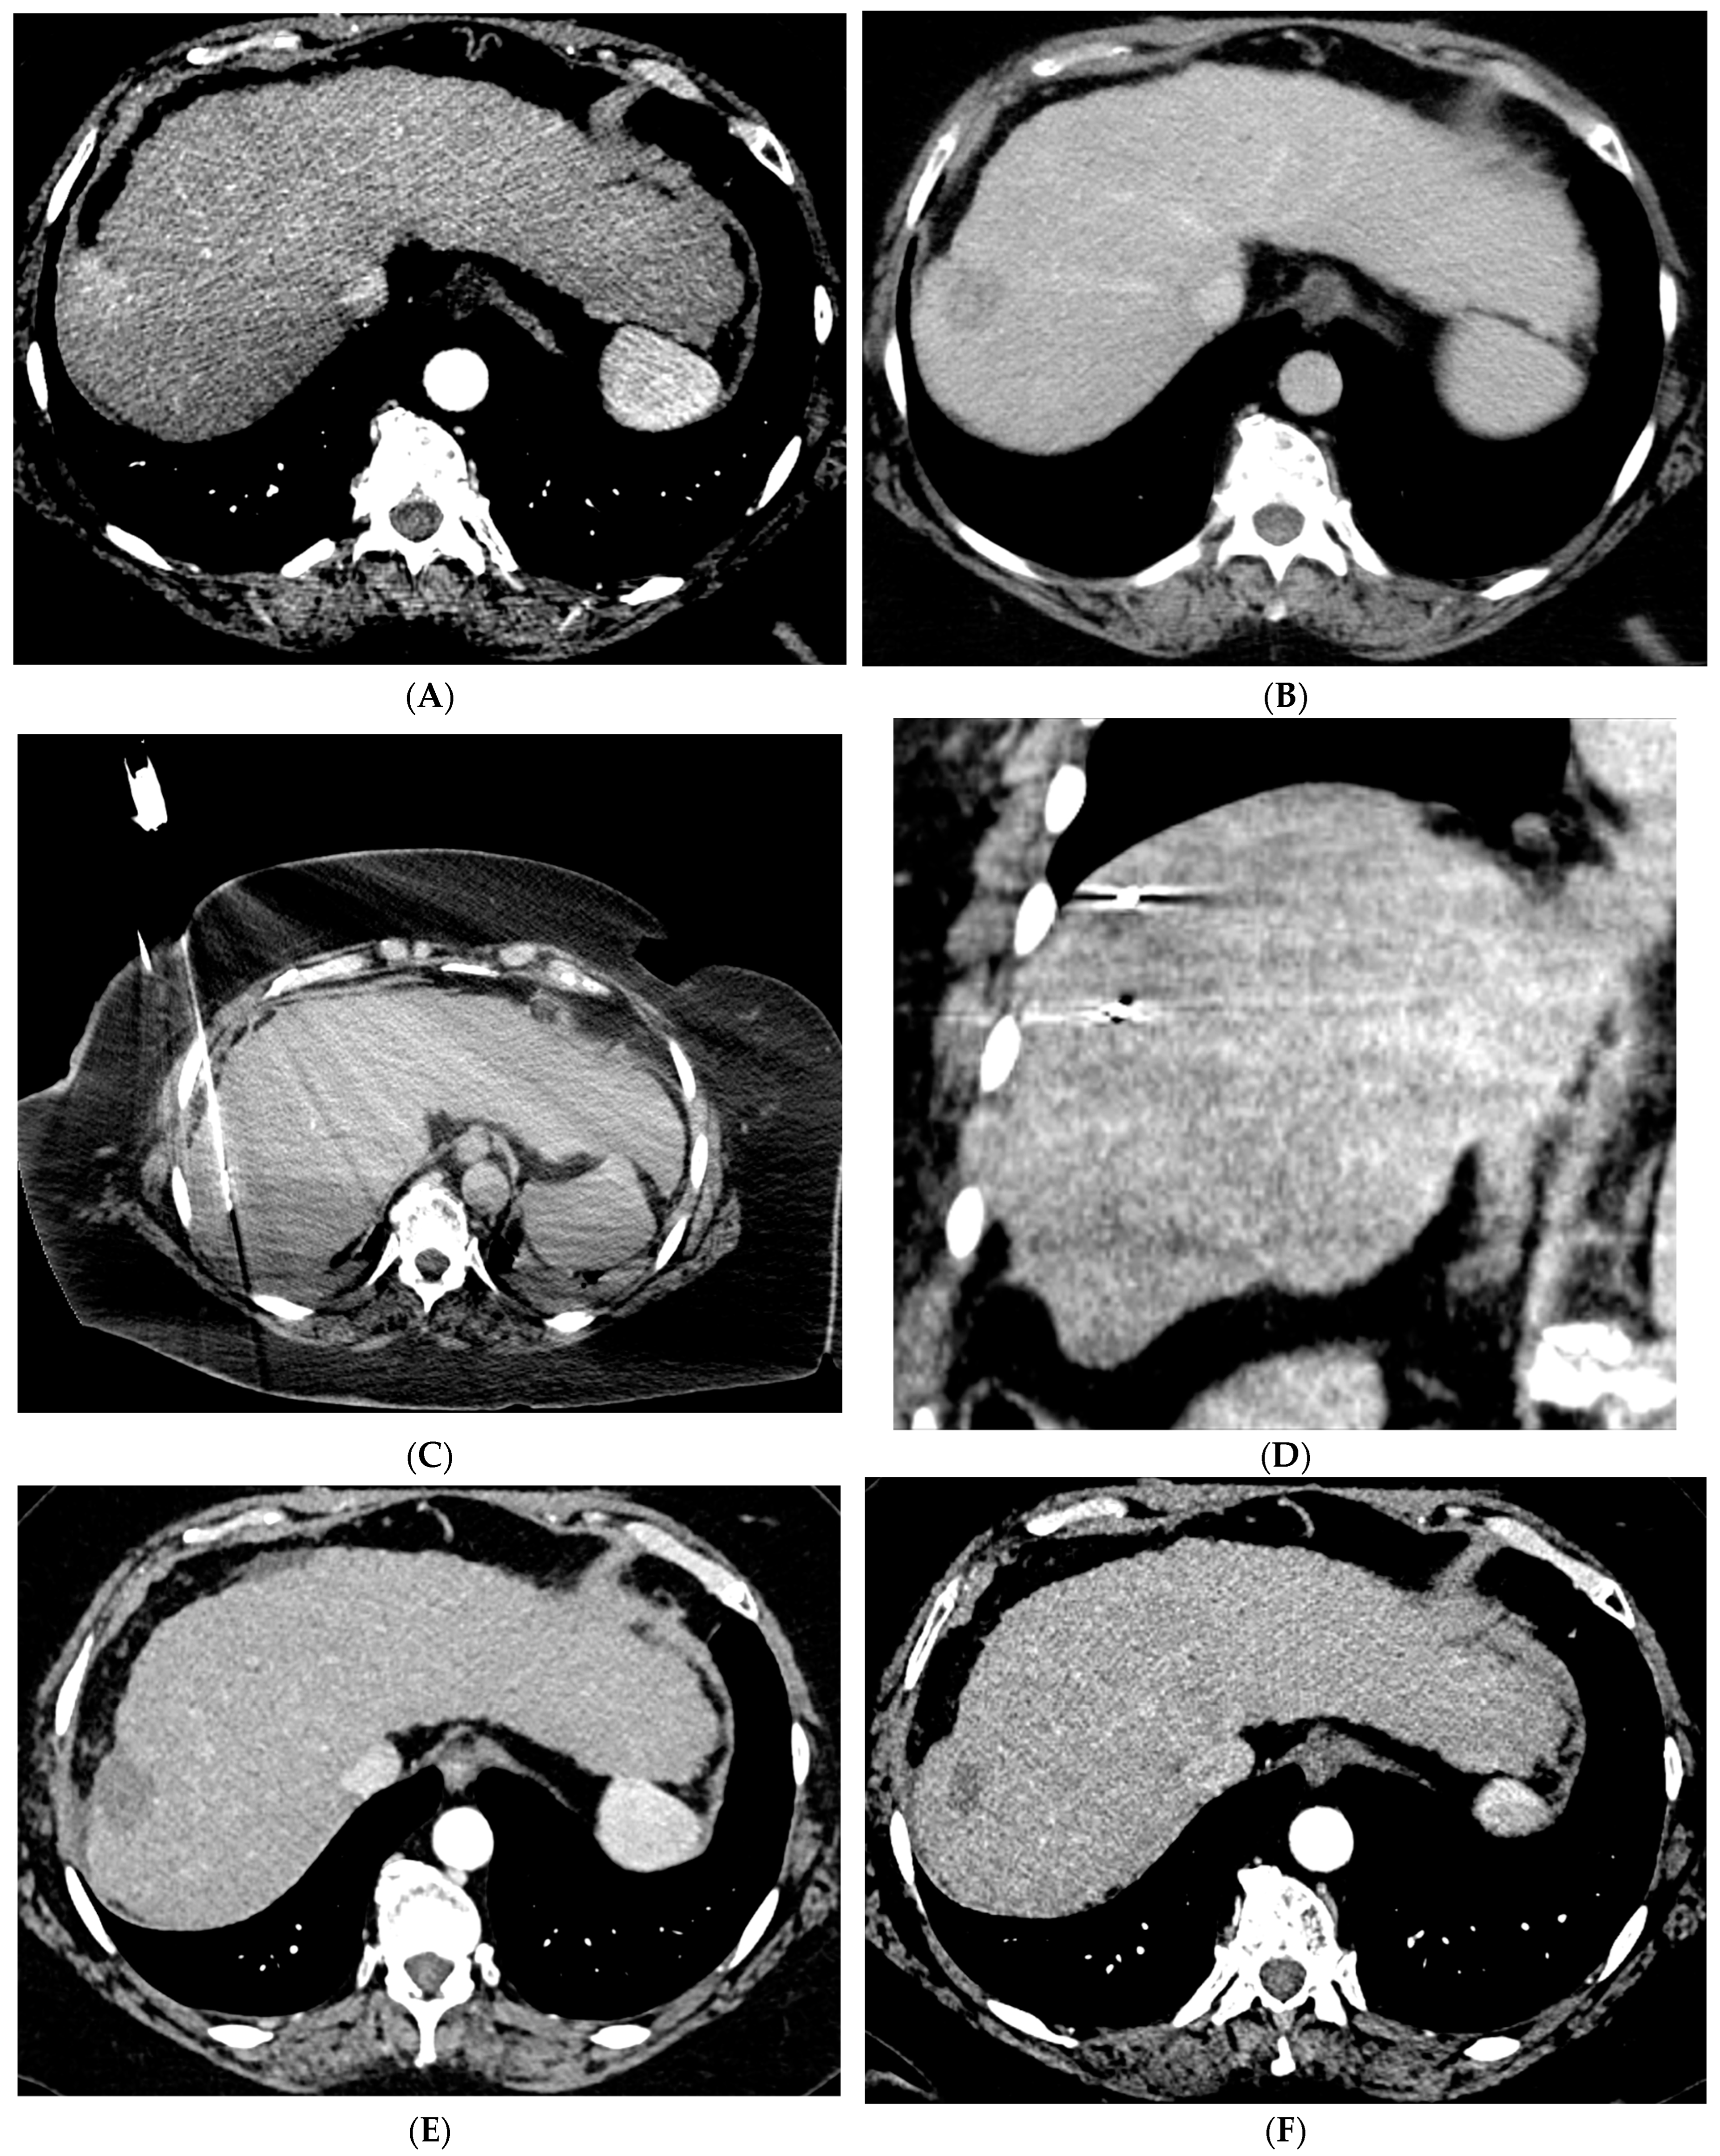

Figure 1.

66-year-old woman with cirrhosis secondary to autoimmune hepatitis and HCC, treated with microwave ablation. (A) Arterial phase MRI showing a 3.5 cm arterially enhancing mass in the periphery of segment 7. (B) Delayed phase MRI demonstrating washout of the mass. Intraprocedural axial (C) and coronal (D) CT images demonstrating probe placement bracketing the mass. (E) Arterial phase MRI one month post ablation showing no residual viable tumor. (F) Arterial phase MRI one year post ablation demonstrating no residual or recurrent viable tumor and involution of the ablation cavity.